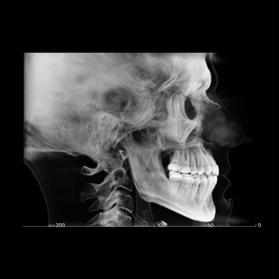

Clinical evaluation showed a mild Class III skeletal pattern with a constricted maxilla, mildly dolichofacial and straight

profile (Figure 1). Full adult dentition was present with all third molars extracted. Maxillary and mandibular incisors were normoclined. The maxillary midline coincided with the facial midline, and the mandibular midline was 2 mm to the right of the facial midline. There was a 2 mm to 5 mm lateral open bite on the right side from the second molar to the lateral incisor, and the maxillary occlusal plane was canted to the left of the interpupillary line. A lateral tongue thrust into the open bite was noted on swallow.

The right side was in posterior crossbite and there was an edge-to-edge anterior bite with wear on the maxillary central incisors. Mild gingival recession was noted, but soft tissue was generally within normal limits. CBCT analysis found no radiographic evidence of osteoarthritis in the TMJ joints, nor osseous or apical pathology involving the maxillary or mandibular teeth. His airway was not constricted. Initial report from the myofunctional therapist indicated that the patient never developed a mature swallow sequence and had a bilateral posterior tongue thrust.

Figure 1. Initial records.